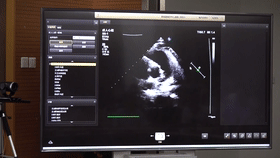

5G遠程會診現場,西安國際醫(yī)學中心心內科張衛(wèi)澤主任、超聲科陳姍姍主任打開4K高清顯示器,屏幕上立刻出現了商洛國際醫(yī)學中心的B超畫面,一位醫(yī)生正在為患者做心臟B超,隨著探頭的轉動,超聲機器上的畫面清晰可見,雖然兩家醫(yī)院相距一百多公里,但畫面流暢,沒一點拖沓。